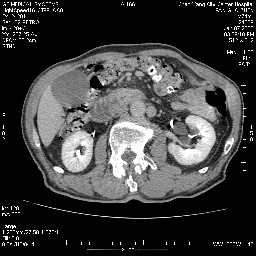

女,74岁,呕吐10余日

壶腹部的占位性病变,考虑为十二指肠癌并梗阻,但脾内多发性低密度区为转移吗?

还有胃、脾之间可见有侧支循环建立。左肾盂积水。

肝胰壶腹占位,考虑-壶腹癌!

胃体部粘膜不规则增厚,胃肠造影也显示充盈缺损-胃溃疡?胃癌?

双肾多发小囊肿;左肾积水。

十二指肠水平段腔内占位伴梗阻,中等度较为均匀的强化,洗脱慢,区域淋巴结显示增多,符合腺癌表现。下腔静脉变异。

十二指肠降段扩张,水平段狭窄成鼠尾状,肠壁明显增厚,胰腺勾突增大成不均匀强化,其内可见低密度区,胆囊增大,1十二指肠水平段腺癌侵犯胰腺勾突可能大,2胰腺癌侵犯十二指肠(只有胆囊增大没有肝内外胆管扩张不好解释)代除外.

上消化道造影见十二指肠结节状充盈缺损,ct增强十二指肠壁局限性增厚并强化,考虑十二指肠壶腹癌?